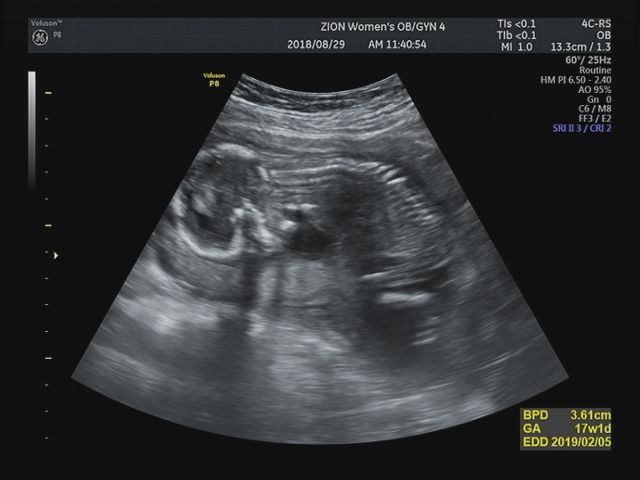

2019.01.28 +38주 2일 출산 D-1일 드디어 내일이면 우리 도도 만나는날!! 따스한 5월에 갑자기 우리가족에...